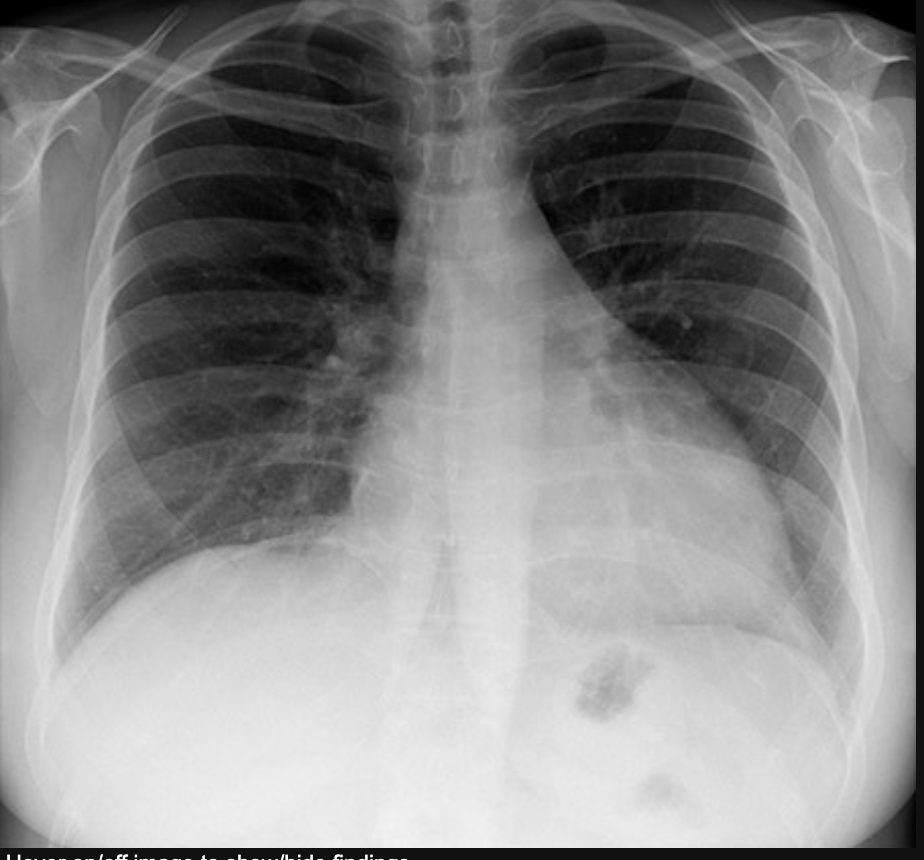

What do we look for in a CXR?

• Water where it is not supposed to be.

Pleural Effusion